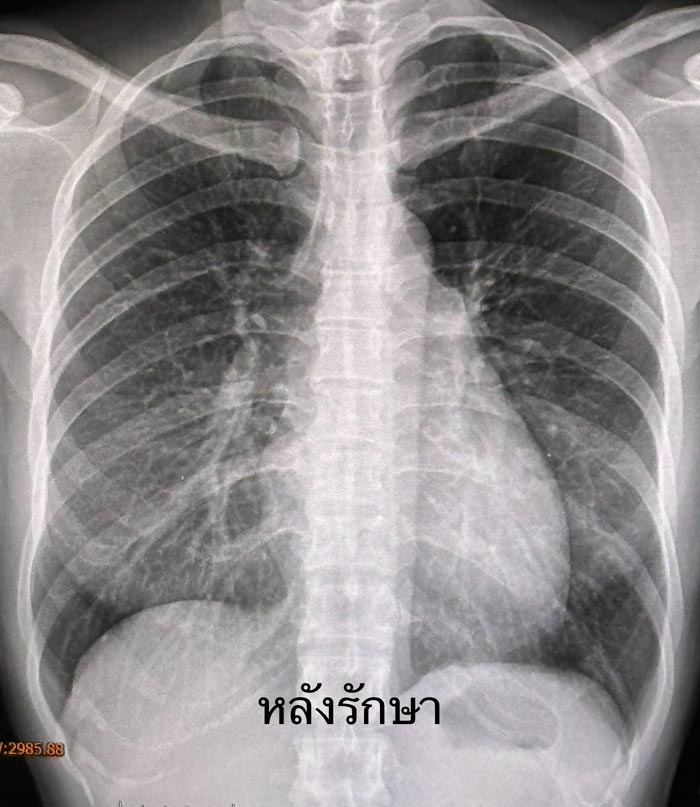

1 เดือนต่อมาผลเสมหะเพาะเชื้อวัณโรค ขึ้นเชื้อวัณโรค M.tuberculosis ไวต่อยารักษาวัณโรคทุกตัว ให้ยารักษาวัณโรค 4 ขนานต่อไปจนครบ 2 เดือน แล้วลดยาเหลือ INH, rifampicin และวิตามิน B6 รับประทานต่อไปจนครบ 6 เดือน ผู้ป่วยแข็งแรงดี ไม่มีไอเป็นเลือด เอกซเรย์ปอดปกติ (ดูรูป)